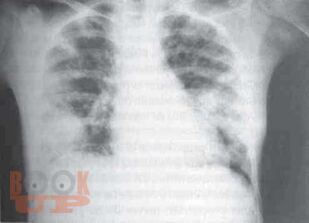

В данном томе многотомного руководства по детским болезням рассмотрены актуальные вопросы пульмонологии, систематизированные в виде современных представлений о заболевании органов дыхания. Приведены новейшие теоретические и клинические данные по анатомо-функциональной характеристике, этиологии, патогенезу, эпидемиологии, патоморфологии, патофизиологии, классификации заболеваний. Представлены методы диагностики и дифференциальной диагностики в детской пульмонологии. Даны практические рекомендации по лечению отдельных форм пульмонологических заболеваний и проведения реабилитационных мероприятий. Руководство иллюстрировано фотокопиями рентгенограмм, томограмм и др.